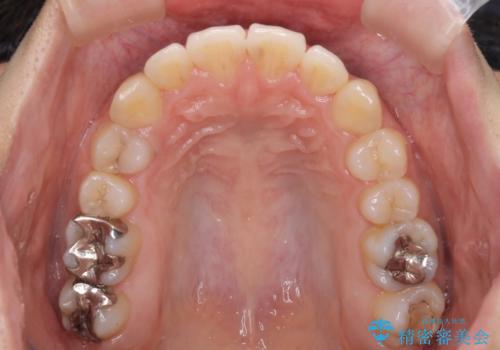

前歯の突出感とデコボコ インビザラインで改善

- 上下前歯のデコボコを気にして来院された患者様です。

インビザラインによる上下歯列の側方拡大と後方移動、IPR(歯と歯の間を削る)にるスペースの獲得により歯列を整えることとしました。

右上の小臼歯は歯根癒着をしており、様々な方法を試みるも動かすことができませんでした。

それでも奥歯のかみ合わせに不自由はなく、歯列をきれいに整えることができました。